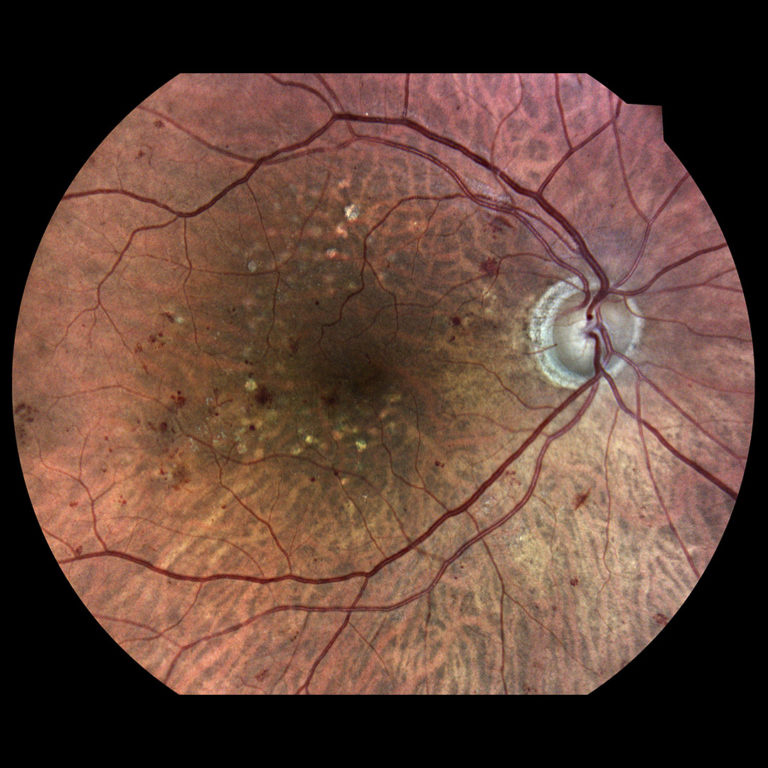

Diabetická retinopatia

Diabetická retinopatia je hlavnou príčinou straty zraku u dospelých vo veku medzi 20 - 74 rokov. Viac ako jedna tretina z odhadovaných 285 mil. ľudí s cukrovkou na celom svete vykazuje príznaky diabetickej retinopatie. Diabetická retinopatia je na vzostupe v dôsledku zvyšujúcej sa prevalancie cukrovky, stárnutia populácie a predlžujúcej sa dĺžky života ľudí s cukrovkou.

- infračervené mapy zvýrazňujúce svetlé a červené lézie/poškodenia